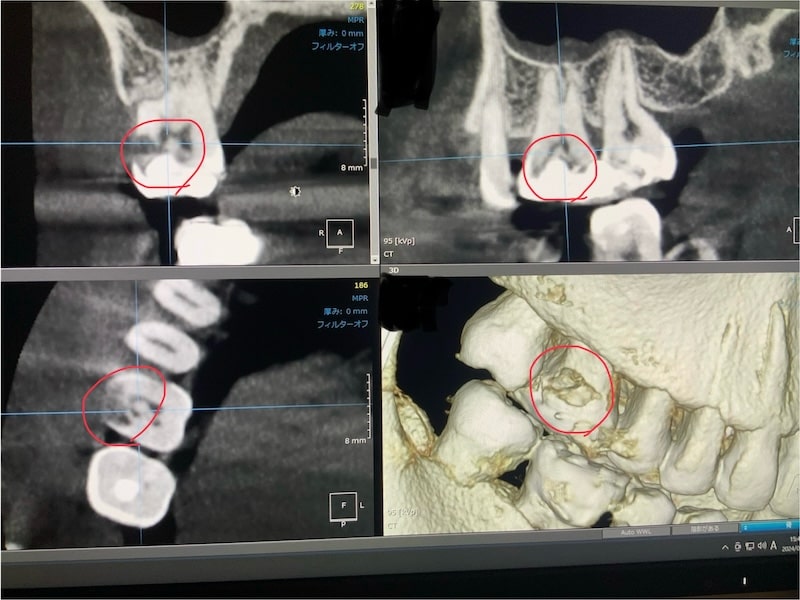

症例9 大臼歯 生活歯髄治療

術前

CT